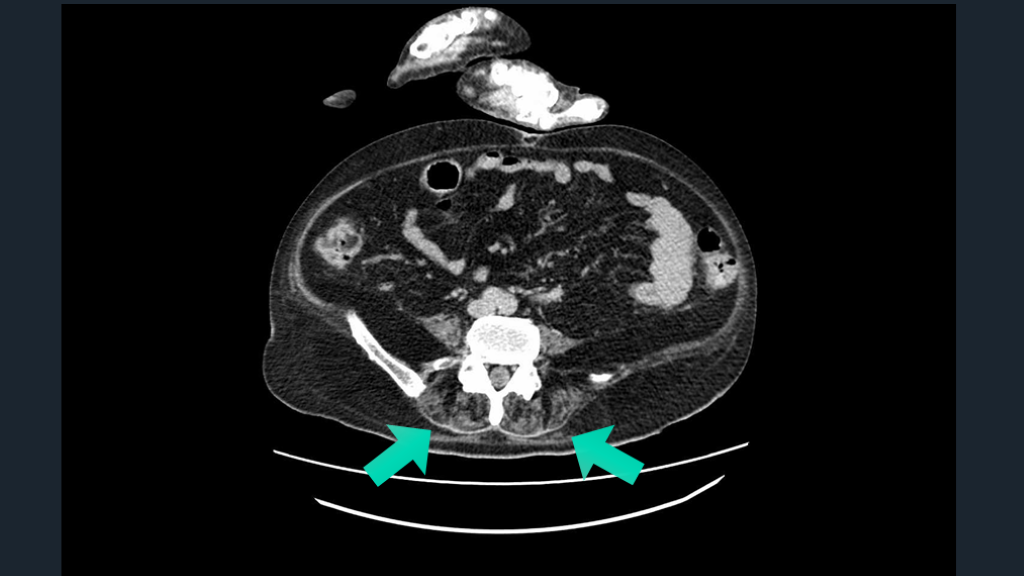

脊髄障害は わかりにくかったりする。 運動感覚障害・膀胱直腸障害を ヒントに。CTでの膀胱所見も。 TIPS

#60.

CASE 70歳男性例。AFでDOAC内服中。 頸部痛で発症した四肢脱力症状。 まずは、硬膜外血腫や脊髄梗塞を鑑別にあげた。 そして、脊髄障害らしさを示唆するヒントを確認していく。

CTで膀胱見てみる。 しっかりした脊髄障害では膀胱直腸障害はないか?を意識して所見を確認する。 CTでの膀胱が緊満しているさまもみる。 脊髄梗塞の鑑別には、CTで大動脈解離も気にする。 解説 Neurologia . 2023;38(6):391-398.

Ochsner J. 2015;15(1):70–73. CTで膀胱拡張を確認